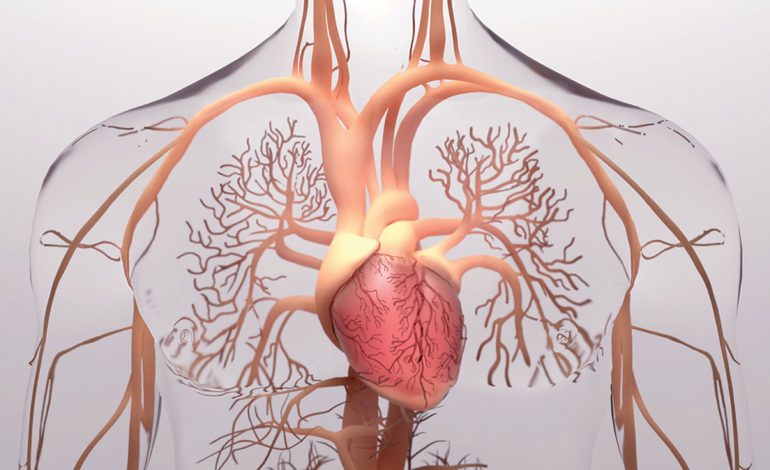

Sistemi i qarkullimit të gjakut

Edhe pse dëmi që tensioni i lartë shkakton fillon si diçka e vogël, sa më shumë qëndron i pakuruar, aq më shumë rrezikon organizmin.

Duke qenë se lidhet direkt me qarkullimin e gjakut, dëmi i parë shkaktohet pikërisht tek muret e enëve të gjakut.

Në kapilarë, arterie dhe vena krijohen çarje të vogla si pasojë e presionit të lartë të gjakut që lëviz në to.

Tek këto çarje grumbullohen molekuka të kolesterolit duke shkaktuar ngushtim e deri në bllokim të tyre.

Nëse diçka e tillë ndodh, furnizimi i gjakut nuk është në kapacitetin maksimal të tij, dhe dëmton organin tek i cili duhet të çonte gjak.

Nga ana tjetër kur enët e gjakut janë të bllokuara, zemra duhet të punojë më shumë gjë që çon në zmadhim të ventrikulave.

Si pasojë mund të shkaktohet dhimbje kraharori apo në rastet më të rënda dhe atak në zemër.